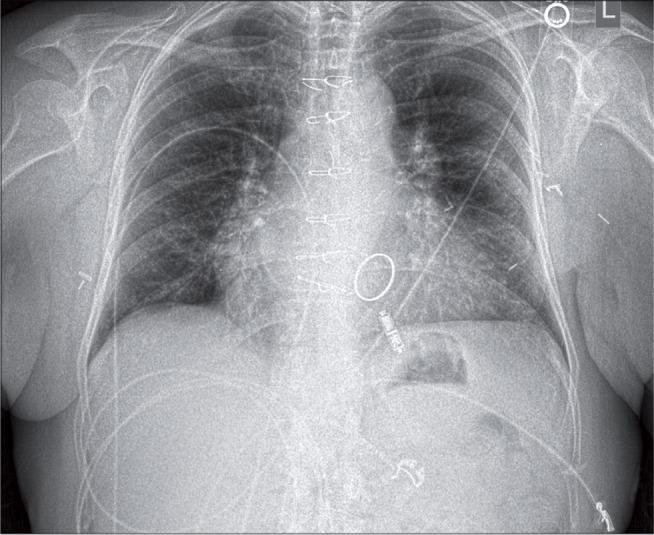

Pacemaker-dependent (PD) patients undergoing implantable cardiac electronic device extraction often must be subjected to temporary pacing interventions. We sought to determine the safety and utility of a leadless pacing system (Micra™; Medtronic, Minneapolis, MN, USA) in patients undergoing system extraction as compared with externalized temporary transvenous right ventricular lead (temp-perm) placement. We performed a retrospective cohort analysis of all patients receiving either permanent Micra™ or temp-perm systems following system extraction from October 2013 to September 2017 at Vanderbilt University Hospital. The Micra™ and temp-perm cohorts included nine and 27 patients meeting the inclusion criteria, respectively. System infection was the most common indication for extraction (67% Micra™, 84% temp-perm), but no patients had active bacteremia at the time of permanent system reimplantation. There was no difference in system type (p = 0.09) or mean lead dwell time extracted (109 versus 81 months; p = 0.93). Procedure times were comparable between the two groups (180 versus 194 minutes; p = 0.74). Patients receiving Micra™ systems had shorter hospital stays after extraction (two versus eight days; p < 0.005), with no difference in major complications (11% versus 15%; p = 0.78) or 30-day (11% versus 7%; p = 0.77) or 90-day (11% versus 11%; p = 0.45) mortality. No reinfections were observed in either group at 90 days. Implantation of the Micra™ pacing system in select PD patients after system extraction is feasible and appears to reduce the hospital length of stay as compared with the use of temp-perm systems.

接受植入式心脏电子设备拔除的起搏器依赖(PD)患者通常必须接受临时起搏干预。我们试图确定与外置临时经静脉右心室导线(临时-永久)置入相比,无导线起搏系统(Micra™;美敦力公司,美国明尼苏达州明尼阿波利斯)在接受系统拔除的患者中的安全性和实用性。我们对2013年10月至2017年9月在范德比尔特大学医院接受系统拔除后植入永久性Micra™或临时-永久系统的所有患者进行了回顾性队列分析。Micra™组和临时-永久组分别有9例和27例患者符合纳入标准。系统感染是拔除的最常见原因(Micra™组为67%,临时-永久组为84%),但在永久性系统重新植入时没有患者出现活动性菌血症。系统类型(p = 0.09)或拔除的平均导线留置时间(109个月对81个月;p = 0.93)没有差异。两组的手术时间相当(180分钟对194分钟;p = 0.74)。接受Micra™系统的患者拔除后住院时间较短(2天对8天;p < 0.005),主要并发症(11%对15%;p = 0.78)或30天(11%对7%;p = 0.77)或90天(11%对11%;p = 0.45)死亡率没有差异。90天时两组均未观察到再感染。在部分PD患者系统拔除后植入Micra™起搏系统是可行的,并且与使用临时-永久系统相比,似乎可以缩短住院时间。